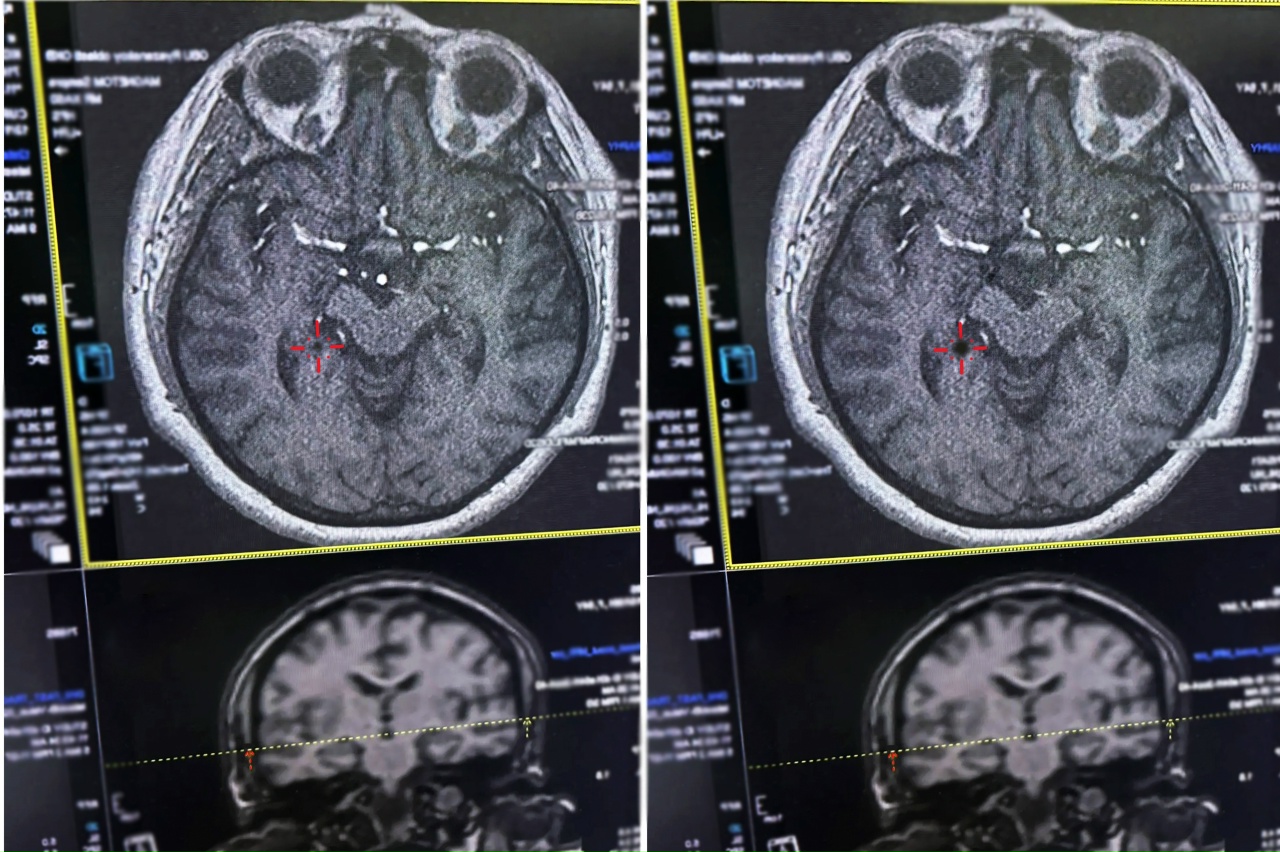

В Рязани врачи областной клинической больницы оперативно спасли женщину с инсультом

По пути в больницу состояние ухудшилось – парализовало правую сторону тела, мучили сильные головные боли. Однако медики успели принять меры именно в первые жизненно важные 4,5 часа («терапевтическое окно») после начала приступа.

Источник фото: Министерство здравоохранения Рязанской области